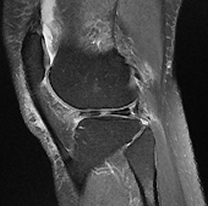

Subchondral Changes

MFC Bone Marrow Oedema and Subchondral Cyst

MFC Subchondral Oedema and Cyst